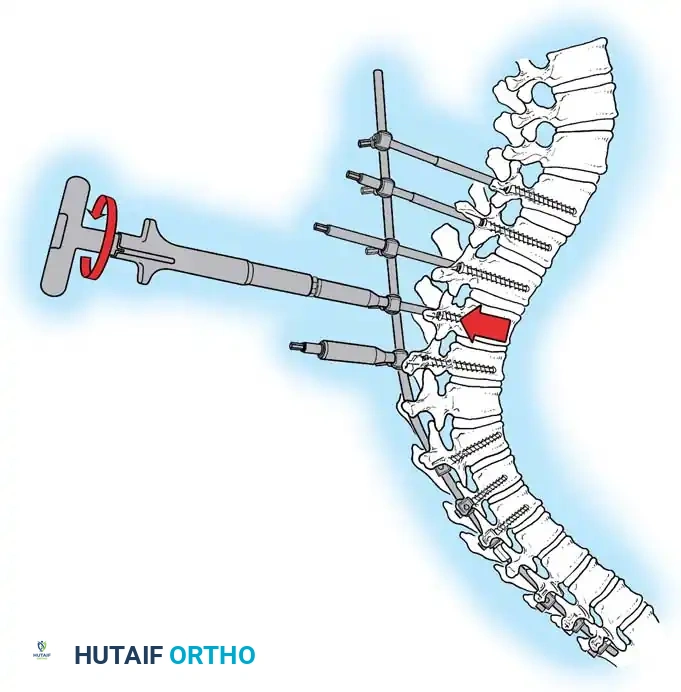

4. Rod Contouring and Reduction

Two rigid rods (typically 5.5mm or 6.0mm Cobalt Chrome or Titanium) are meticulously contoured. The rods must be under-contoured relative to the patient's current deformity but over-contoured relative to the desired final physiological kyphosis (aiming for 40 degrees).

Insertion of the contoured rod into the pedicle screw construct.

The reduction is achieved via a cantilever maneuver. The rods are seated in the distal foundation screws first. Using reduction tubes and set screws, the rod is sequentially drawn into the apical and proximal screws. This maneuver translates the spine to the rod, simultaneously correcting the kyphosis and restoring sagittal balance.

Cantilever reduction maneuver closing the posterior osteotomies and correcting the kyphotic deformity.

5. Apical Compression

Once the rods are seated, sequential compression is applied across the apical screws. This closes the Ponte osteotomies, shortens the posterior column, and acts as a fulcrum to lengthen the anterior column, effectively reversing the biomechanical pathology of Scheuermann disease.